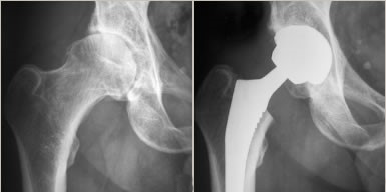

L’arthrose (ou coxarthrose) est l’usure du cartilage de votre hanche. Le cartilage est le revêtement protecteur qui permet aux os de glisser parfaitement l’un sur l’autre, comme un coussinet.

Avec le temps, ce cartilage s’abîme, s’affine et finit par disparaître. Les os se retrouvent alors en contact direct « os contre os ». Ce frottement crée de l’inflammation et devient très douloureux.

On décide d’opérer lorsque le traitement médical ne suffit plus et que la douleur et la raideur deviennent trop invalidantes au quotidien. L’âge n’est pas une limite : l’important est de retrouver une bonne qualité de vie.

Remplacer l'articulation douloureuse.